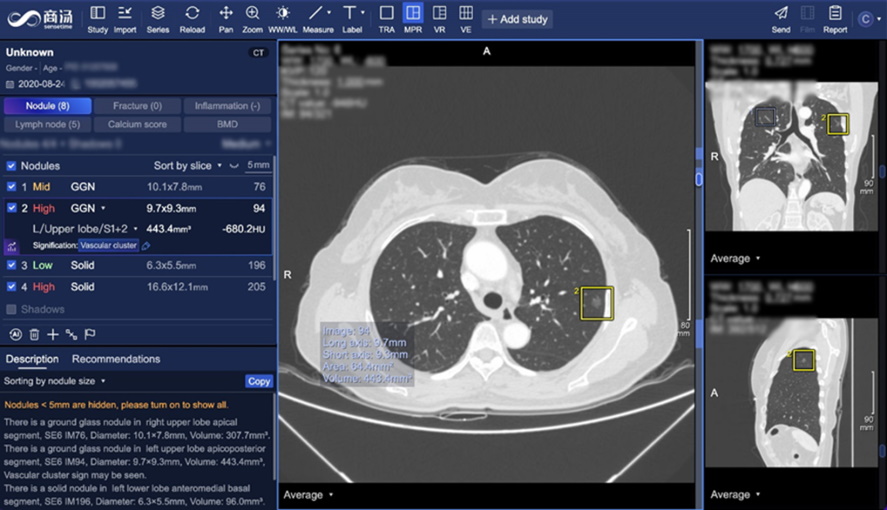

智能精準 AI成為可靠的臨床助手

面對東南亞的肺癌發病率不斷上升,SenseCare在臨床應用中,尤其是在肺結節等早期篩查與管理方面,展現出重要價值。作為醫生的「AI助手」,該系統可在短時間內精準識別CT影像中僅幾毫米大小的肺結節,並智能提示其潛在風險,有效提升篩查效率、降低漏診率。

在患者覆診時,系統更能自動對比不同時間點的影像數據,追蹤病灶大小和密度的變化,並計算其生長速度,協助醫生實現精準化、數碼化的病情評估,制定切合患者所需的治療方案,達到既能避免過度檢查,又能及時診治高風險患者的「雙重目標」,提升整體就醫體驗與質量。

SenseCare系統在IHH醫療(集團)百匯放射科全面落地後,已迅速融入醫生的日常診療流程,成為放射科的「標配工具」。百匯放射科每月進行上千例肺結節覆診,該系統替代了大量重複、繁瑣的人手比對工作,並提供自動化影像分析與量化數據支持,讓醫生能更專注於複雜的病情判斷,釋放醫務人員的寶貴時間,而患者亦能更快獲取檢查結果,享受更具前瞻性的健康管理及治療。此舉不僅推動醫院管理效能顯著提升,也促進了患者、醫生與醫療機構的多方共贏。